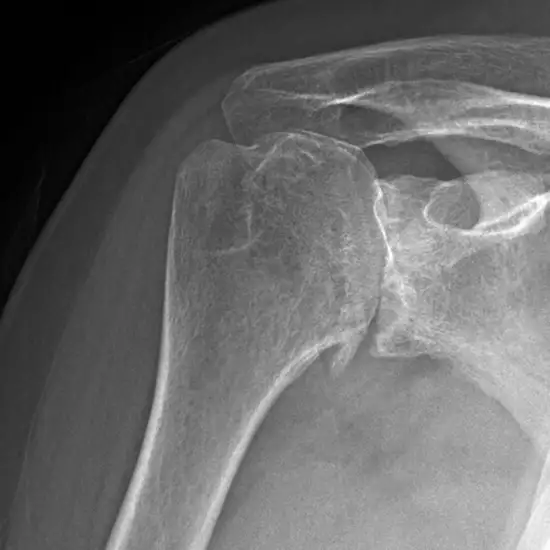

CECT Left Shoulder Joint is a contrast study of the left side of the shoulder joint. In which a dye is injected to evaluate fractures and diseases affecting your Shoulder joint.

Doctors recommend this CT Scan to look for any underlying problems in the left shoulder concerns like:

• Left shoulder trauma

• To evaluate fracture of the left shoulder joint

• To diagnose the cause of pain in the left side of the shoulder

• Tumors or abnormal growth

• Arthritis of the left shoulder

• Shoulder dislocation